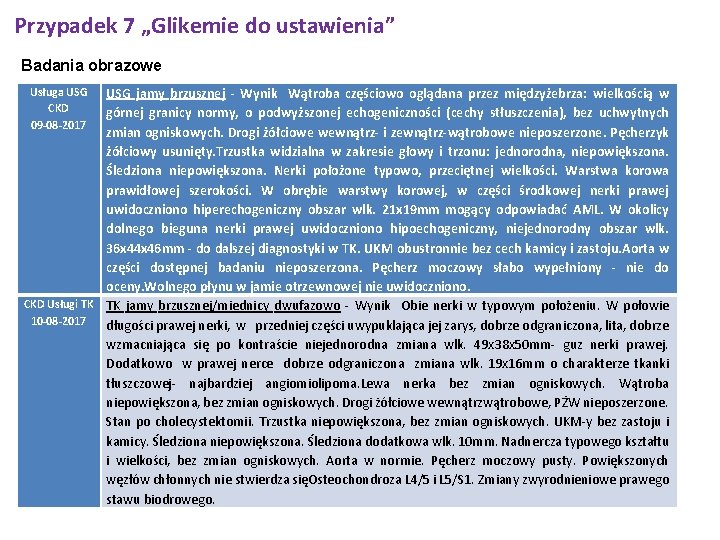

Przypadek 7 „Glikemie do ustawienia” 58 -letnia pacjentka została przyjęta do Kliniki w trybie planowym 08. 2017 z powodu wysokich glikemii (do 200 mg%) pomimo przyjmowania metforminy, przestrzegania diety cukrzycowej i wysiłku fizycznego. Cukrzyca u chorej została rozpoznana w czerwcu bieżącego roku, bez stanów hipoglikemicznych. W wywiadzie ponadto przewlekła obturacyjna choroba płuc, hipecholesterolemia, nadciśnienie tętnicze. W trakcie pobytu obserwowano zadowalające poziomy glukozy oraz odsetek hemoglobiny glikowanej 6. 4%. Chorą przeszkolono z zasad diety cukrzycowej. Wykonano USG jamy brzusznej które ujawniło dwie zmiany w obrębie nerki prawej

Przypadek 7 „Glikemie do ustawienia” Badania obrazowe Usługa USG CKD 09 -08 -2017 USG jamy brzusznej - Wynik Wątroba częściowo oglądana przez międzyżebrza: wielkością w górnej granicy normy, o podwyższonej echogeniczności (cechy stłuszczenia), bez uchwytnych zmian ogniskowych. Drogi żółciowe wewnątrz- i zewnątrz-wątrobowe nieposzerzone. Pęcherzyk żółciowy usunięty. Trzustka widzialna w zakresie głowy i trzonu: jednorodna, niepowiększona. Śledziona niepowiększona. Nerki położone typowo, przeciętnej wielkości. Warstwa korowa prawidłowej szerokości. W obrębie warstwy korowej, w części środkowej nerki prawej uwidoczniono hiperechogeniczny obszar wlk. 21 x 19 mm mogący odpowiadać AML. W okolicy dolnego bieguna nerki prawej uwidoczniono hipoechogeniczny, niejednorodny obszar wlk. 36 x 44 x 46 mm - do dalszej diagnostyki w TK. UKM obustronnie bez cech kamicy i zastoju. Aorta w części dostępnej badaniu nieposzerzona. Pęcherz moczowy słabo wypełniony - nie do oceny. Wolnego płynu w jamie otrzewnowej nie uwidoczniono. CKD Usługi TK TK jamy brzusznej/miednicy dwufazowo - Wynik Obie nerki w typowym położeniu. W połowie 10 -08 -2017 długości prawej nerki, w przedniej części uwypuklająca jej zarys, dobrze odgraniczona, lita, dobrze wzmacniająca się po kontraście niejednorodna zmiana wlk. 49 x 38 x 50 mm- guz nerki prawej. Dodatkowo w prawej nerce dobrze odgraniczona zmiana wlk. 19 x 16 mm o charakterze tkanki tłuszczowej- najbardziej angiomiolipoma. Lewa nerka bez zmian ogniskowych. Wątroba niepowiększona, bez zmian ogniskowych. Drogi żółciowe wewnątrzwątrobowe, PŻW nieposzerzone. Stan po cholecystektomii. Trzustka niepowiększona, bez zmian ogniskowych. UKM-y bez zastoju i kamicy. Śledziona niepowiększona. Śledziona dodatkowa wlk. 10 mm. Nadnercza typowego kształtu i wielkości, bez zmian ogniskowych. Aorta w normie. Pęcherz moczowy pusty. Powiększonych węzłów chłonnych nie stwierdza sięOsteochondroza L 4/5 i L 5/S 1. Zmiany zwyrodnieniowe prawego stawu biodrowego.

Przypadek 7 „Glikemie do ustawienia” Diagnostykę rozszerzono o TK jamy brzusznej w którym opisano guz nerki wielkości 49 x 38 x 50 mm oraz zmianę o charakterze najprawodopodobniej angiomyolipoma. Przypadek chorej konsultowano telefonicznie z doktorem Mariuszem Szewczykiem z Kliniki Urologii WSSZ im Kopernika - chora kwalifikuje się do nefrektomii (najprawdopodobniej częściowej), Chorą wypisano z Kliniki w stanie ogólnym dobrym, z zaleceniami jak poniżej. Dalsza opieka u Lekarza Rodzinnego (poradnia POZ) Wydano skierowanie do Oddziału Urologii celem kwalifikacji do nefrektomii Opieka ambulatoryjna w Poradni Diabetologicznej. Regularne pomiary ciśnienia tętniczego Regularne pomiary glikemii. Dieta cukrzycowa. Systematyczne przyjmowanie leków: 1. Metformax 1000 mg 1 tabletka rano, w południe i wieczorem 2. Oxodil 2 razy 1 wdech (według zaleceń pulmonologa) 3. Atoris 20 mg 1 tabeltka wieczorem 4. Tritace 5 mg 1 tabletka wieczorem Czas pobytu 08. 2017 -11. 08. 2017 3 dni